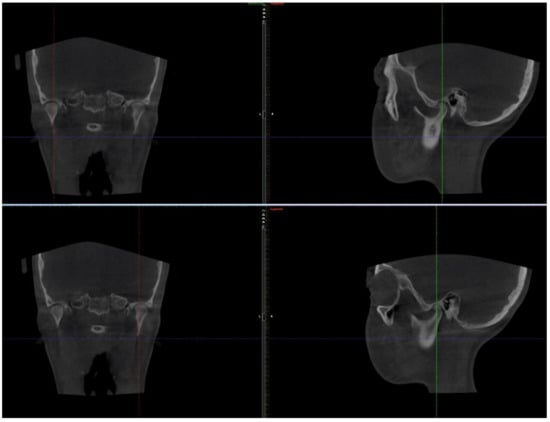

2.1. Initial Diagnosis and Initial Surgical Management

2.3.2. Second Phase of Treatment—2017—Bite-Blocks and Transpalatal Arch